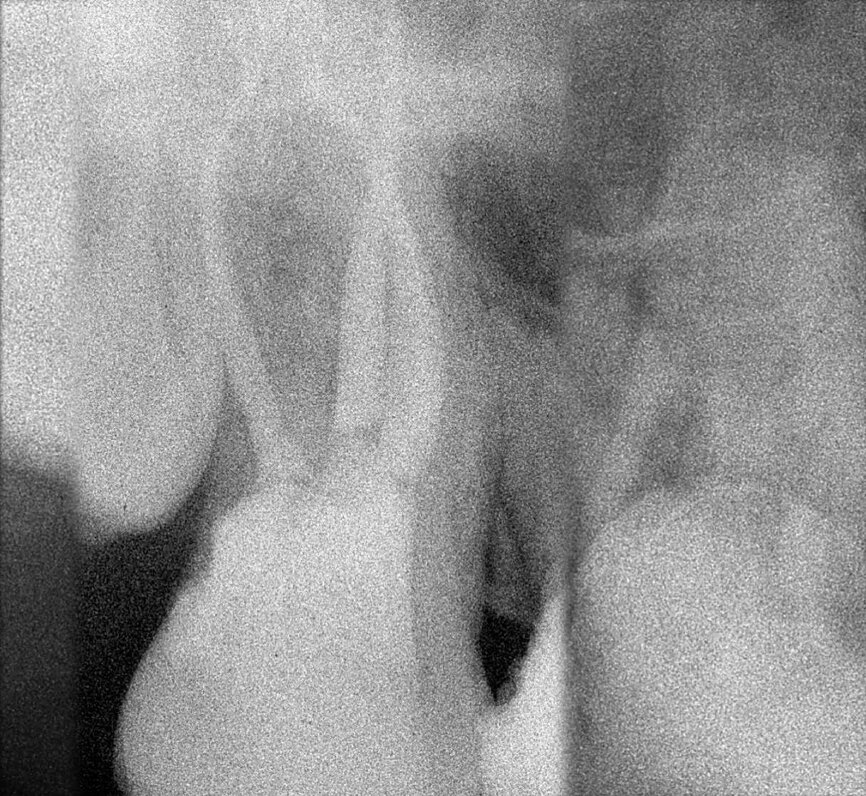

Le cas avec lequel je souhaite commencer mon exposé clinique est un exemple parfait de la difficulté à définir l’origine des symptômes d’un patient, par l’examen d’une simple radiographie intraorale. Non seulement l’examen 2D ne permet pas d’établir avec certitude la présence d’une lésion, mais surtout, il est impossible d’en déterminer la taille, la morphologie et le type. Au contraire, une analyse de l’imagerie 3D offre une image claire de la situation clinique. Chez ce patient, les coupes coronales et sagittales révèlent la présence d’une importante lésion s’étendant de l’apex de la racine mésiale de cette molaire jusqu’à la zone de furcation, tandis que les coupes axiales nous permettent d’analyser précisément l’anatomie endodontique et, en particulier, la forme de la racine mésiale, qui apparaît fusionnée avec la racine palatine. Un panorama complet du cas peut donc guider le processus de décision et orienter le plan de traitement vers une modalité bien précise de traitement (Figs. 1–4).

Il en va tout autrement pour la prémolaire mandibulaire présentée dans les figures 7 à 9 où, malgré l’absence de signes radiologiques de lésion et le traitement endodontique visiblement correct réalisé par un autre confrère, le patient se plaint d’une douleur persistante, qui est à la fois spontanée et déclenchée par un test de percussion de la dent. Dans ce cas, l’excellent traitement endocanalaire réalisé précédemment semble indiquer le besoin de recourir à une approche endodontique chirurgicale, susceptible de garantir un taux de réussite plus élevé que celui d’un simple retraitement. Étant donné le doute sur le diagnostic, nous avons décidé de réaliser un examen 3D et celui-ci révèle une lésion endodontique causée par un canal lingual resté sans traitement. Grâce à ce diagnostic exact, il devient possible d’envisager une intervention ciblée sur la pulpe restante, et de réaliser un traitement efficace du canal non traité.